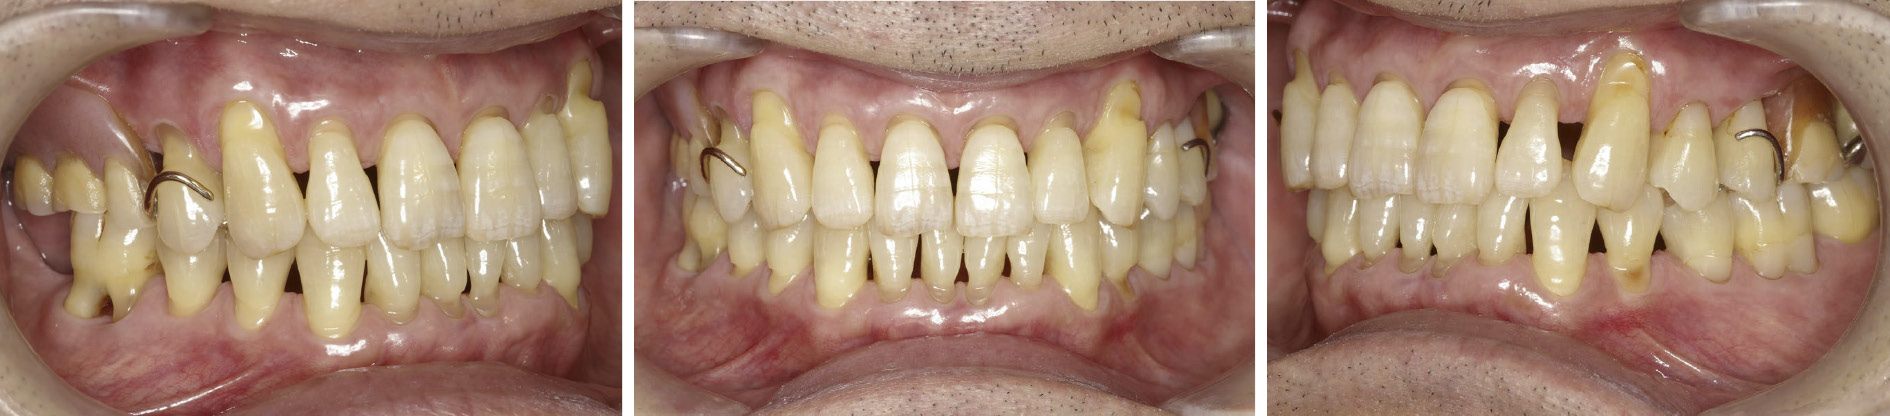

1. 現症 1) 口腔内所見(図1)18,17,16,28,38,48の欠損が認められるがこれは患者が就寝時にクレンチング習癖があり,咬合性外傷が原因で抜歯に至ったと考えられる。15に金属冠が装着されている。全顎的に歯肉の腫脹,歯石の沈着が認められた。

初診時の口腔内写真 1991年10月

SPT移行時の口腔内写真 1992年4月